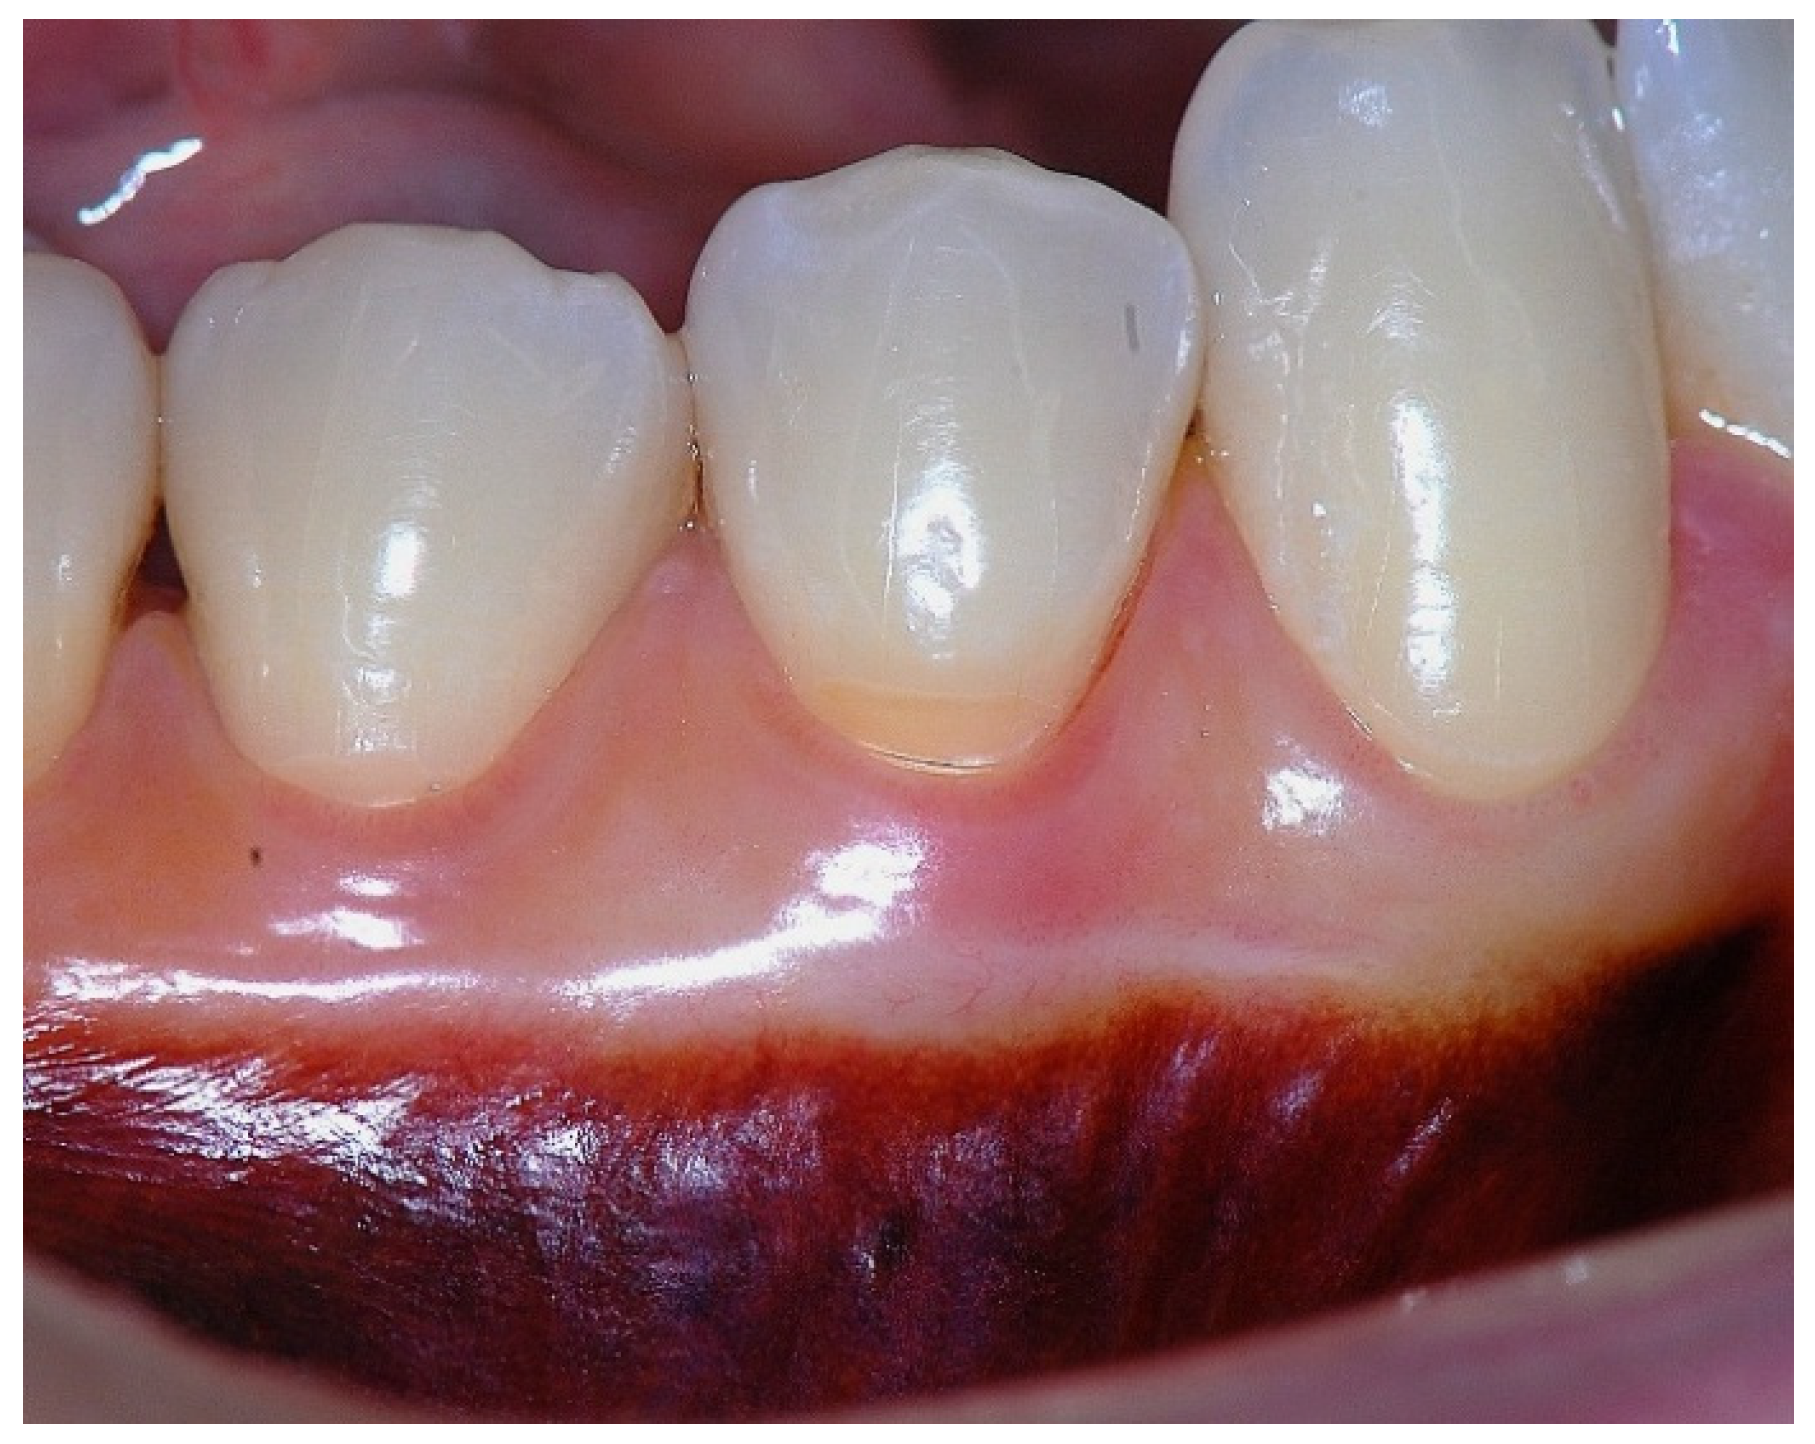

Figure 3. Apical displacement of the gingival margin observed during deep lip retraction.

In a clinical scenario characterized by 2 mm of keratinized tissue and a sulcus depth of 1 mm, a stable and mechanically resistant connective tissue attachment is not present [1]. This is attributable to the fact that most connective tissue fibers inserting into the root surface are associated with non-keratinized, mobile mucosal tissues (Figure 1), which are elastic in nature and therefore incapable of stabilizing the gingival margin (Figure 2 and Figure 3). In contrast, when these fibers are embedded within keratinized tissue, they are firmly anchored to both the tooth and alveolar bone and are comparatively immobile, thereby contributing to gingival margin stability (Figure 4, Figure 5 and Figure 6).